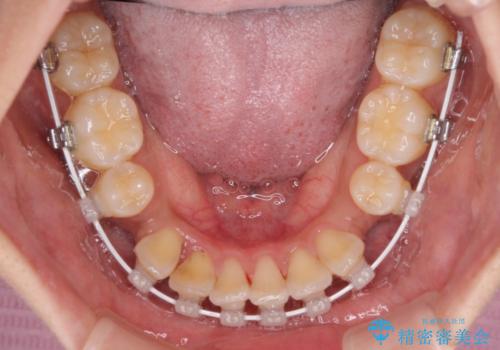

- 前歯のデコボコやクロスバイトと上顎の前突感による口の閉じにくさを気にして来院された患者様です。

目立たない装置を希望されたので、上顎が裏側装置のハーフリンガルを選択し、上下左右の小臼歯(計4歯)を抜歯して矯正治療を行うこととしました。

表側のワイヤー矯正に比べると治療期間は長く、費用も高額となりますが、どうしても目立たせたくないという方にはお勧めの抜歯矯正です。